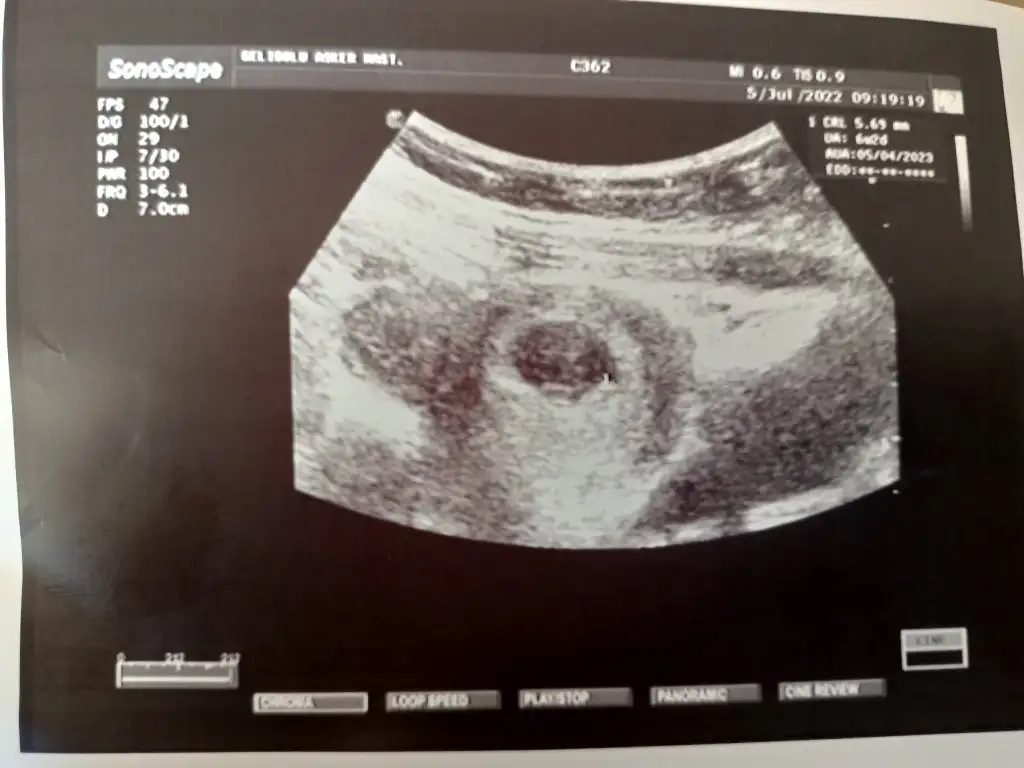

Keseden cinsiyet tahmini

Başka varmı daha belli olan sanki benim oğlumun kesesine benziyor biraz ama içimden de kız geçti 😁

Fasulye gibi ya erkek diyorum tabi ben bilir kişi değilim unutmayın 😊😊rabbim gönlünüzdekini nasip etsin hayırlısı sağlıklı insallah